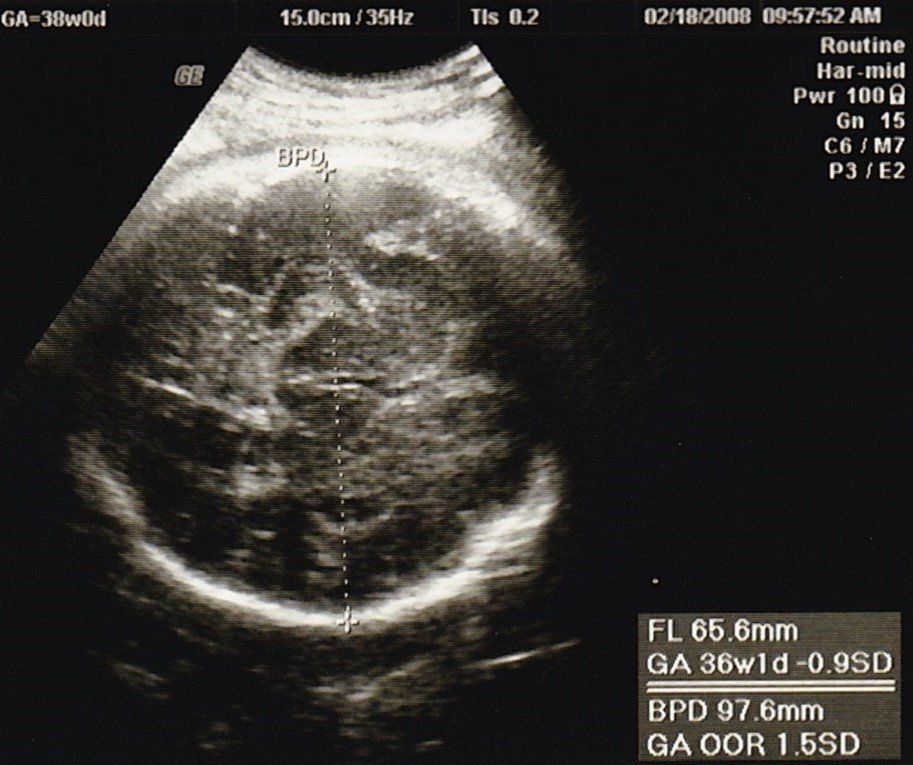

妊娠38週目のエコー写真

このころ、ママ友から続々と「出産しました」メールが届き始めました。10時間以上陣痛に苦しんだり、産後あちこちに痛みが出たりと、リアルな情報にドキドキもしましたが、「トイレは前かがみがいい」とか、「円座クッション、授乳クッションがあるといい」など、産後にかなり役に立つ情報も得られて心強かったです。診察では全く赤ちゃんが降りてくる気配がなく、そろそろ生まれてほしいと思うように。